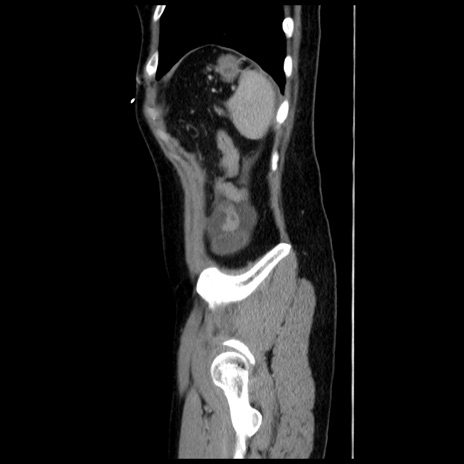

症例10(矢状断像)

【症例】 50歳代女性

【主訴】 腹痛

【現病歴】前日生レバーを食べた。今朝に排便あり。 昼前に突然発症の腹痛を生じ、当院救急外来を受診した。

【既往歴】 子宮筋腫にてで子宮全摘後

【身体所見】 意識清明、腹部:平坦、軟、下腹部やや左を中心に圧痛・反跳痛あり、筋性防御あり

【データ】WBC 7800、CRP 0.07